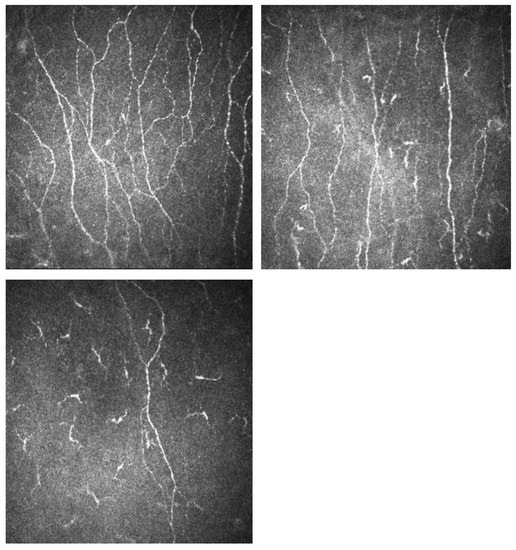

2.5. Corneal Confocal Microscopy

| CNFL (mm/mm2) | 21.08 (2.77) | 20.35 (2.46) | 9.78 (4.58) | 5.17 (1.82) | <0.001 | <0.001 | <0.001 |

| CNFD (no./mm2) | 25.02 (4.27) | 23.06 (6.21) | 11.50 (5.08) | 6.00 (2.59) | <0.001 | <0.001 | <0.001 |

| CNBD (no./mm2) | 26.94 (7.28) | 21.53 (7.27) | 11.51 (6.84) | 5.71 (3.43) | <0.001 | <0.001 | <0.001 |